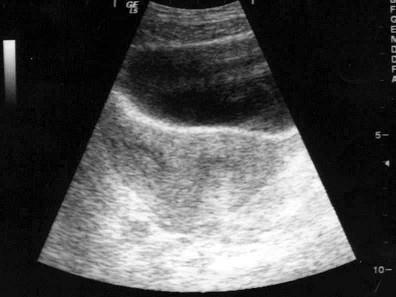

根据超声图像,最可能的诊断是?(?)A.双子宫B.残角子宫C.双角子宫D.纵隔子宫E.以上均是

问题 根据超声图像,最可能的诊断是?(?)

选项 A.双子宫 B.残角子宫 C.双角子宫 D.纵隔子宫 E.以上均是

答案 D